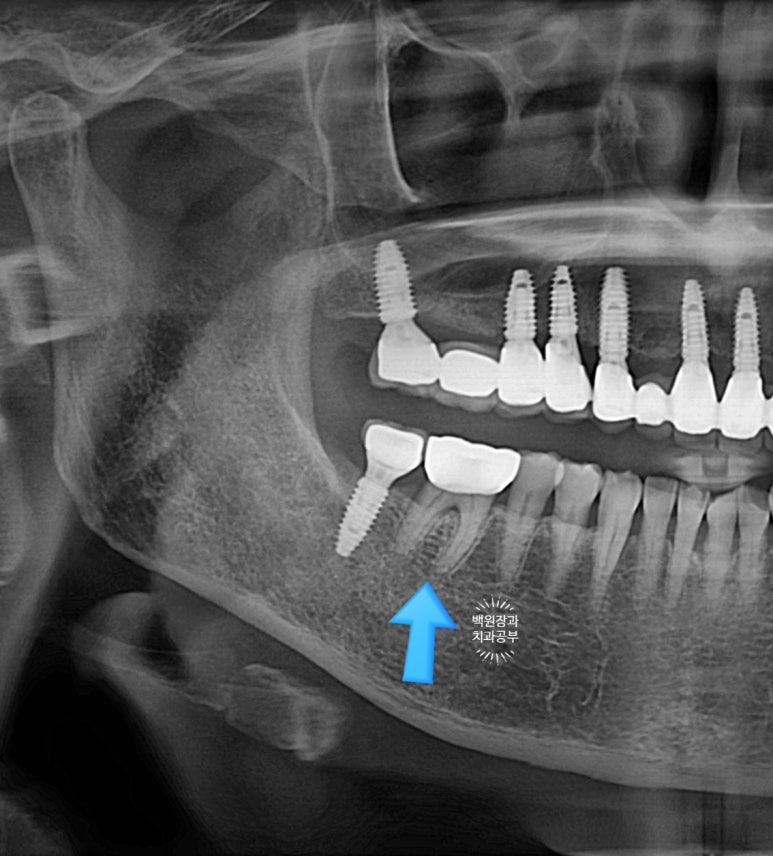

아래 어금니 떼운게 떨어졌어요. 썩은 것 같아요.

: 큰어금니 골드인레이 탈락하고 2차 충치 발견!

사진상에서 금니가 보이시나요?

떨어져서 가지고 오신 것을 제가 끼워놓은 상태입니다.

왜냐! 2차충치가 있음을 더욱 명확히 보여드리기 위해서입니다.

오래 전에 붙여놓은 골드 인레이 주변으로 2차 치아우식증 (2차 충치)가 발생하여 그 틈으로 접착제가 녹아 골드인레이가 떨어진 것이었어요.

저 골드인레이를 제거하면 하방에 분명한 2차 충치가 있습니다.!!!